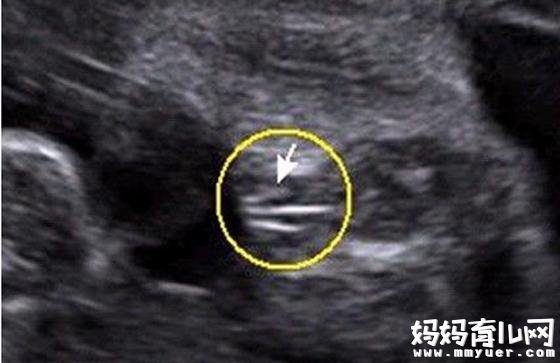

三条白线是明显的女宝特征,如果没有看到明显的三条白线,就看两腿之间有没有突出的东东,且中间有小凹槽的,就是女宝宝。